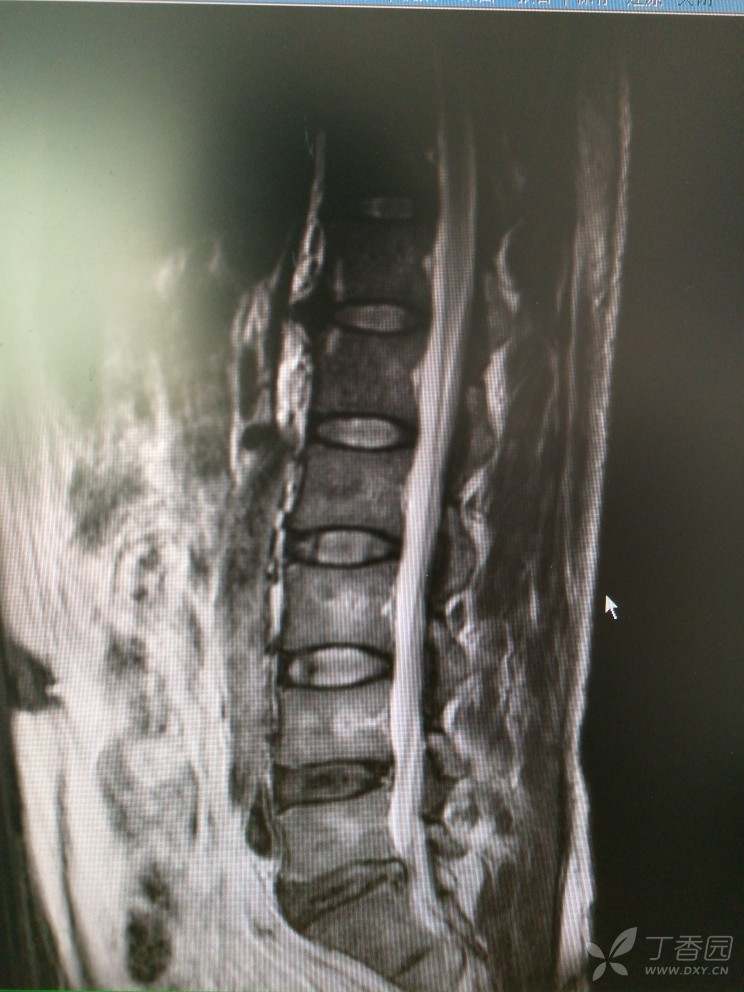

入院查MRI

我想问还是考虑L4/5 L5/S1椎间盘的变性引起的吗?